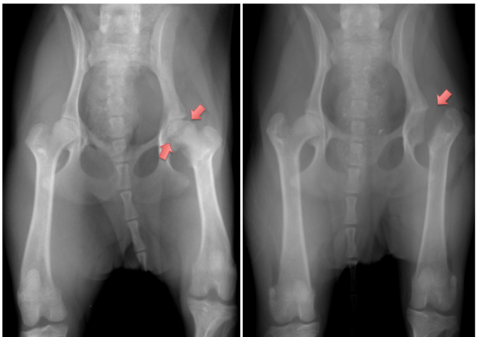

レッグぺルテス

(大腿骨頭壊死症)

成長期に発症する遺伝性疾患で、小型犬に多く認められ、股関節を形成する大腿骨の頭側部への血液供給が不足し、骨頭が壊死してしまう病気です。重篤な場合は、非常に強い痛みを伴い、神経的な疾患とまちがえるほど歩行が困難となります。

ただし、初期はなかなか症状を示さず、見逃されやすい疾患の一つです。残念ながら、レッグぺルテスが発症してしまうと完治させることはできませんが、壊死した骨頭を取り除くことにより、強い痛みはなくなり、日常生活には問題ない程度の歩行や運動、散歩ができるまでに回復することができます。

ただし、早期発見・早期治療を怠ると、痛みで使わなかった足の筋肉が萎縮してしまい、手術をしても回復までに長期間のリハビリが必要になることがあります。